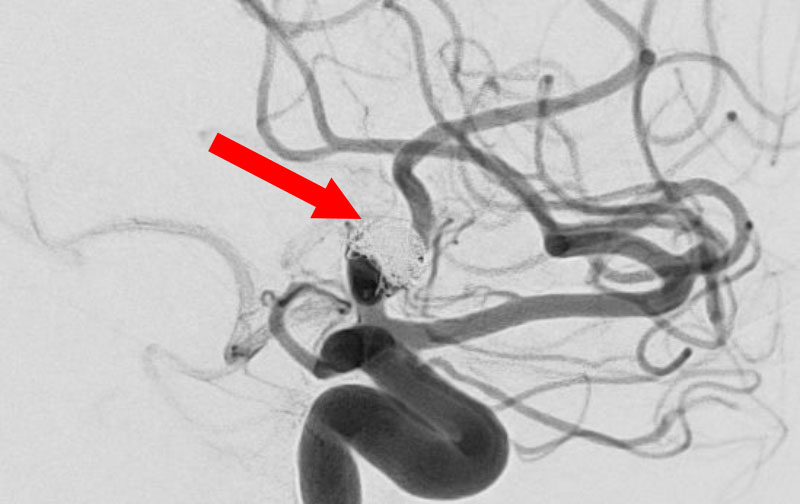

脳動静脈奇形

20代

愛知県の病院

No.1570 手術前

No.1570 手術中

No.1570 手術後